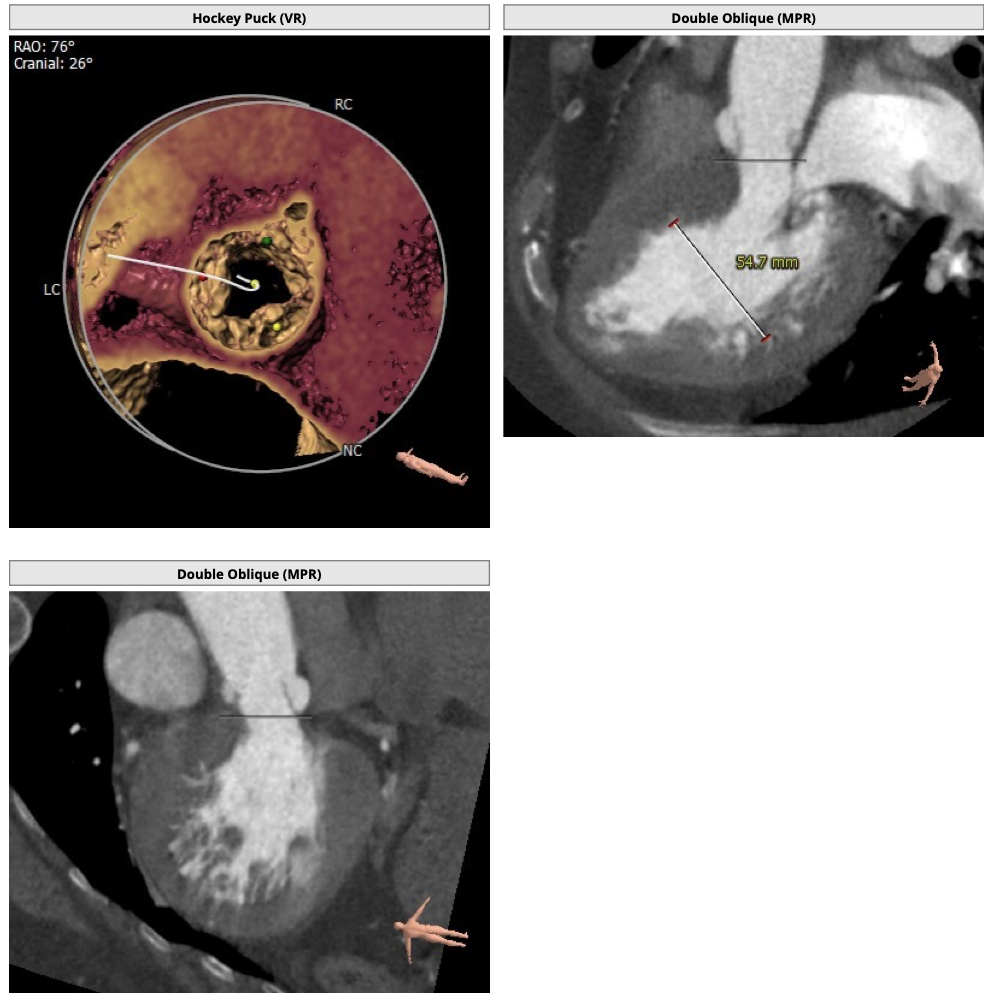

主动脉CT

难点分析:

*患者为四叶瓣,单纯返流,瓣膜锚定具有有一定难度,对释放瓣膜的把控要求高;

*右冠高度可,但左冠高度稍低,具有一定冠脉风险;

*心脏角度略大,释放瓣膜时,瓣膜与瓣环同轴性差。